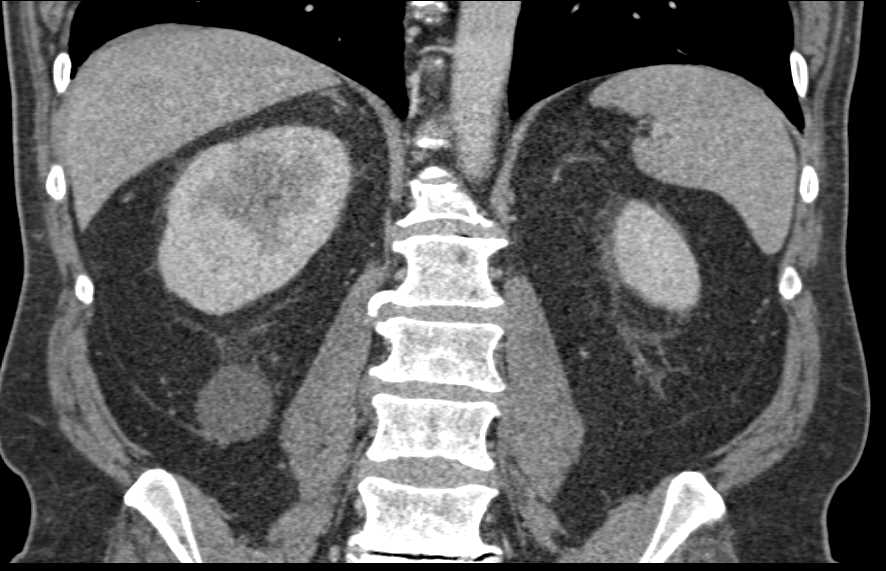

Acute Pyelonephritis Right Kidney